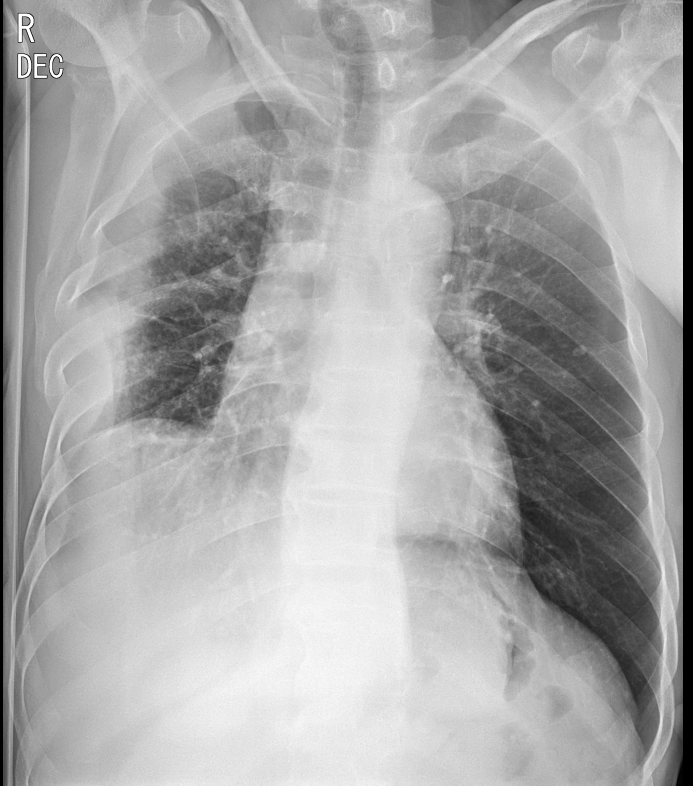

2. decubitus view ; 옆으로 누워 촬영하는 흉부 x ray

옆구리를 바닥에 대고 누워서 촬영한 영상은 다음과 같은 사진을 보여준다.

바로 pleural effusion(흉수)가 있거나 의심되는 상황에서 촬영하게 된다. 물병에 물을 담고 병을 세우거나 눕힐 때면 물은 중력에 의해 바닥에 깔리게 된다. 마찬가지로 흉수는 흉강안쪽에 차는 물이기 때문에 서있는 자세에서는 흉강의 가장 아래쪽 갈비뼈와 diaphragm이 만나는 위치인 CPA(costophrenic angle) 쪽으로 물이차게 된다. 따라서 chest PA에서는 해당 부분이 예리하지 않게 blunting 되는 모습을 보인다면 흉수를 의심할 수 있다. 양이 적을 경우엔 애매한 소견이 나타날 수 있는데, 이런 경우 decubitus view를 촬영하게 되면 흉수가 있는지 없는지 알 수 있게 된다.

위 사진을 예시로 보면 Chest PA로는 환자의 우측 흉강에만 흉수가 보인다. decubitus view를 촬영해 보면 우측으로는 흉수가 많이 보이고, 좌측은 적지만 흉수가 있어 보임을 알 수 있다.